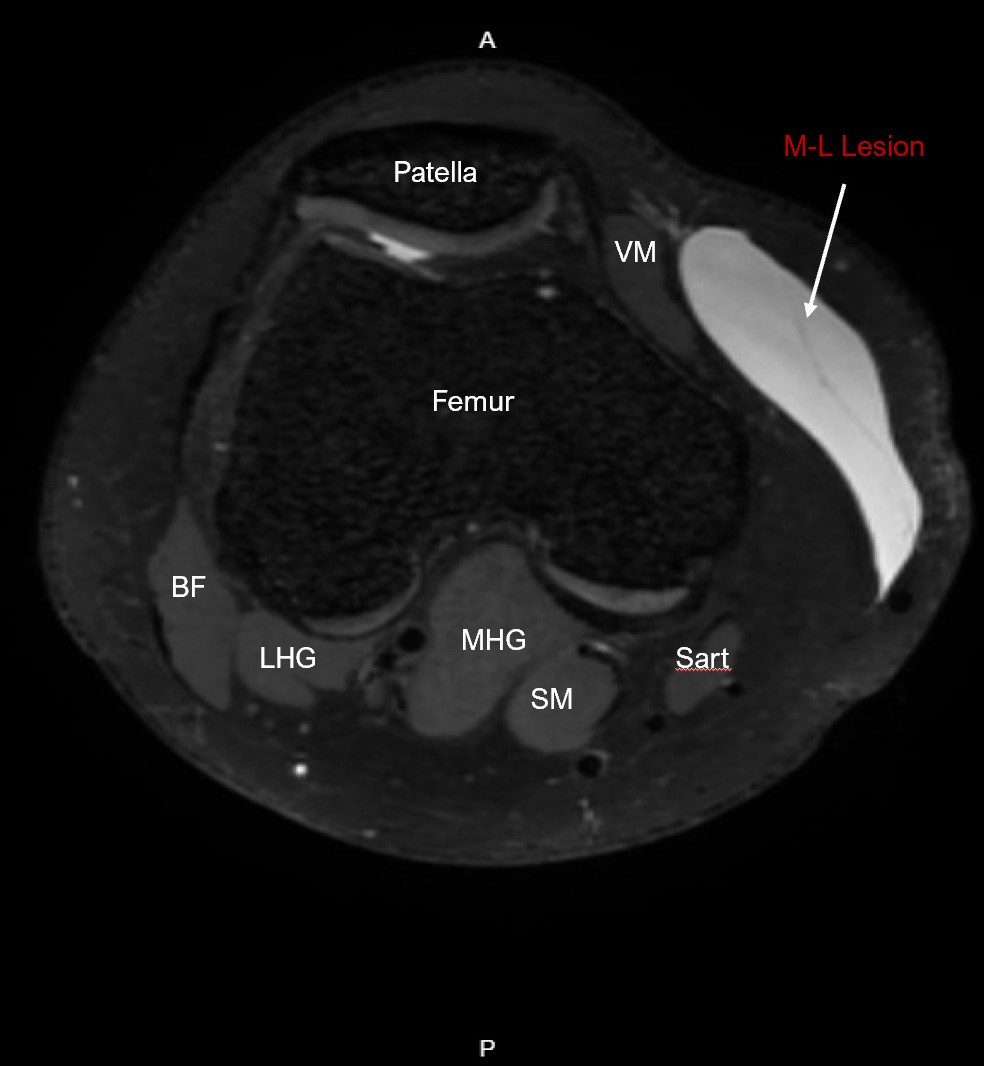

Correlating labeled axial reformat MRI of the Morel-Lavallee Lesion.